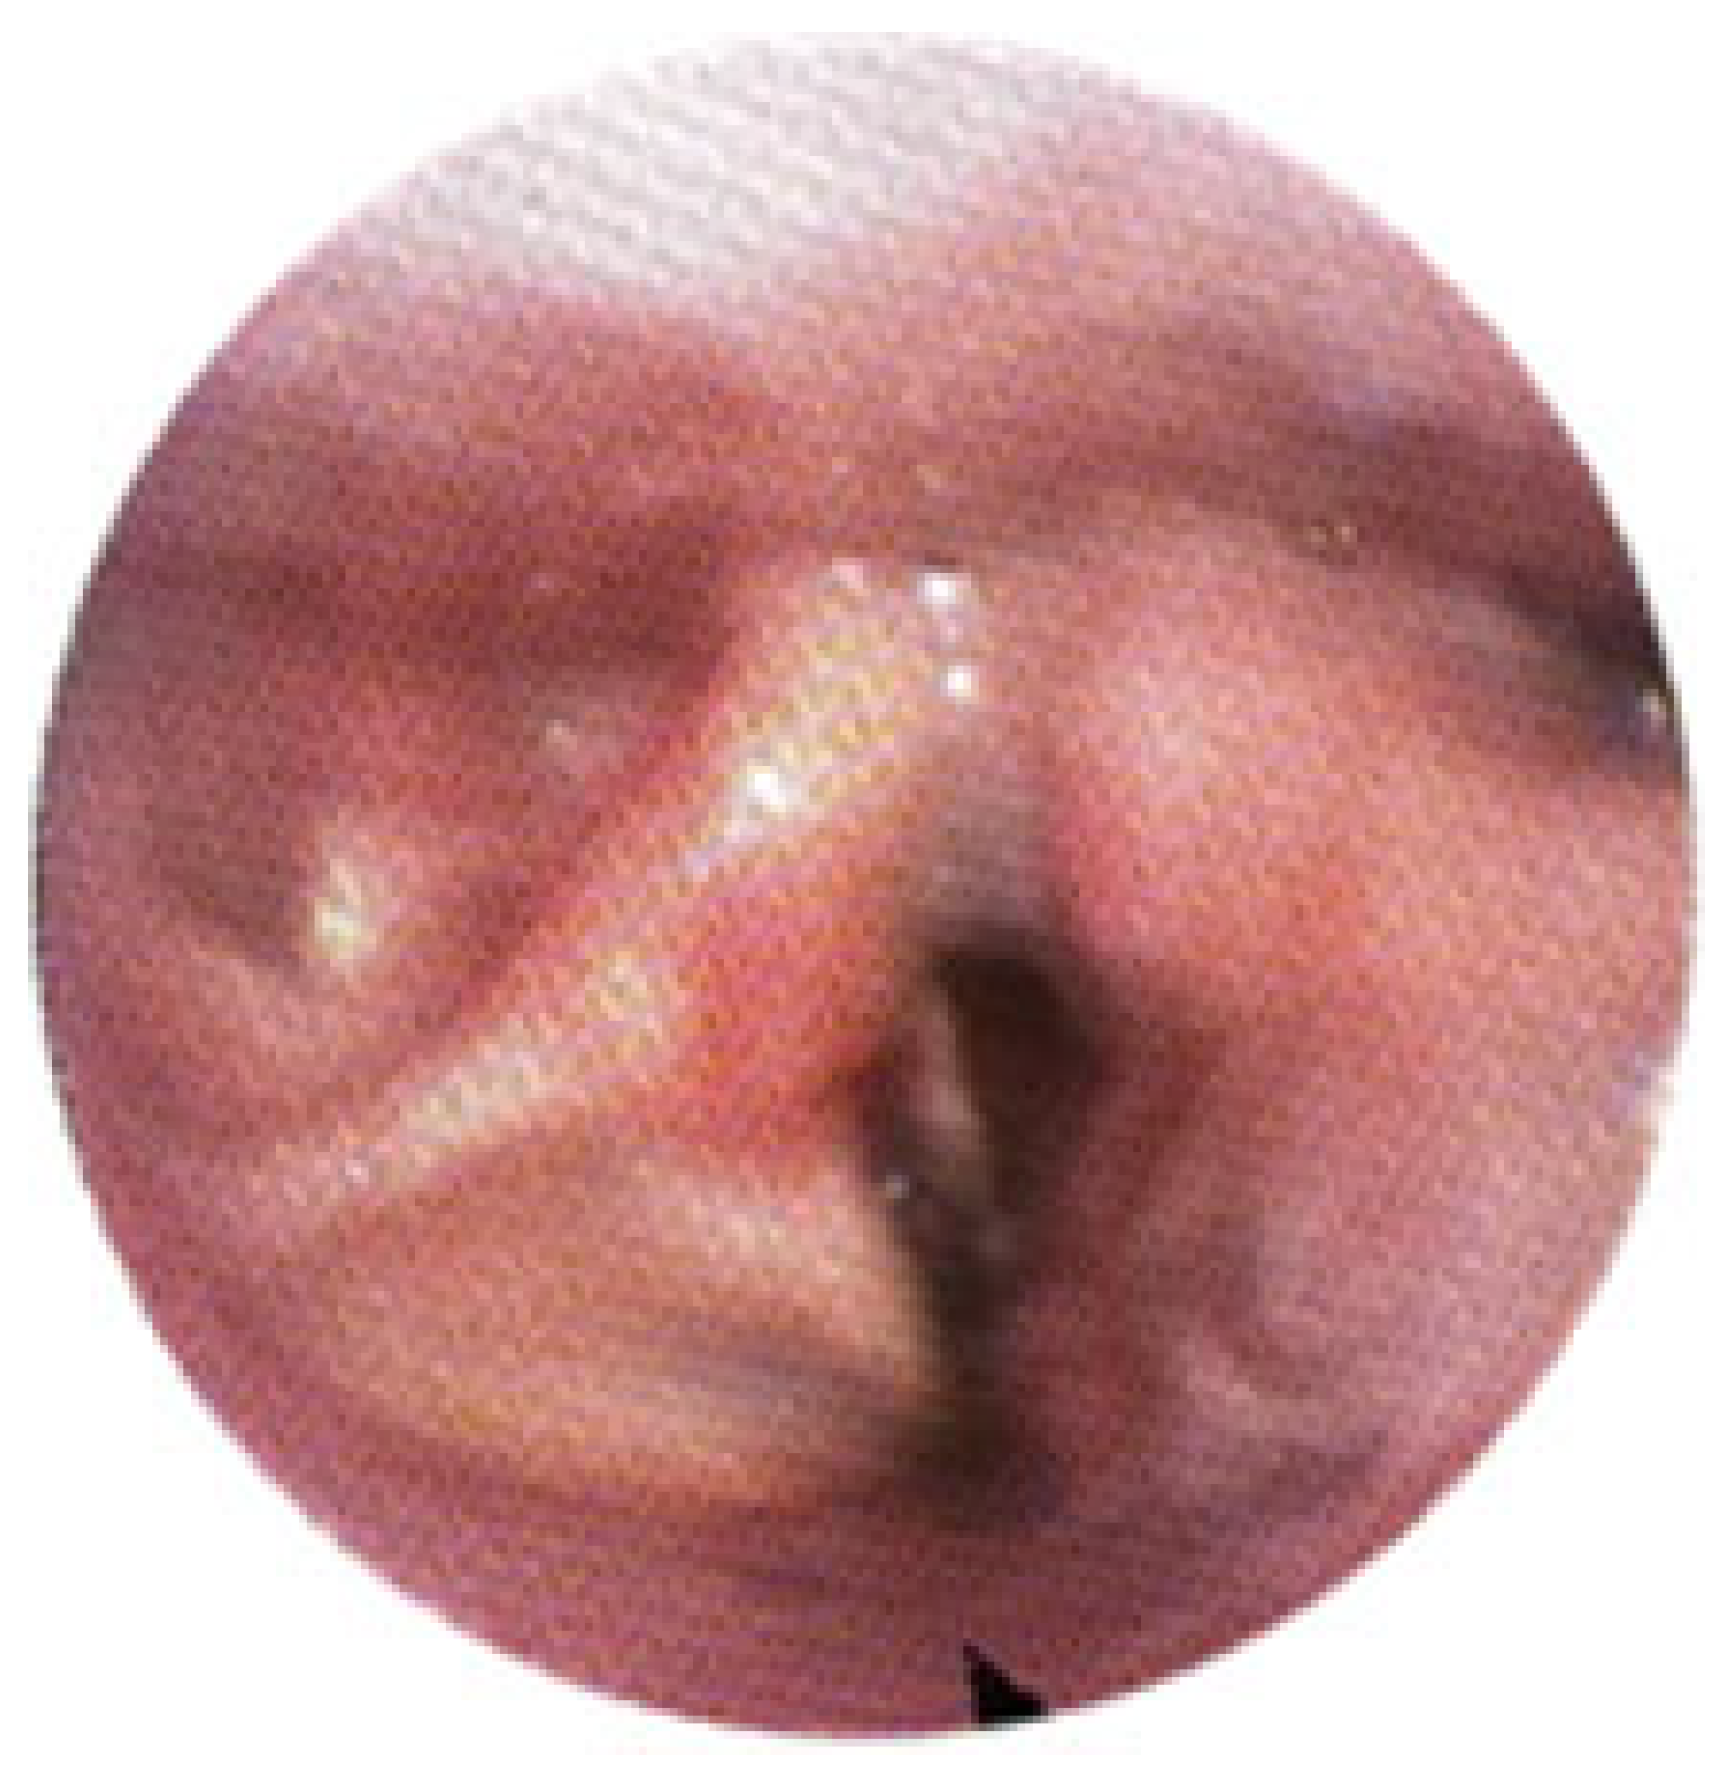

3.2. Clinical Outcomes

- The third case involved a 47-year-old female who developed localized mucosal necrosis secondary to a hematoma, which was associated with significant tenderness. The patient managed the condition with local wound care, and the lesion healed completely within 11 days without the need for systemic therapy (Figure 10).